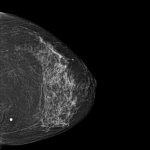

Na imagem abaixo podemos ver como é uma leitura realizada por IA de um exame de mamografia de uma paciente com câncer de mama.

mamografia com leitura por inteligência artificial